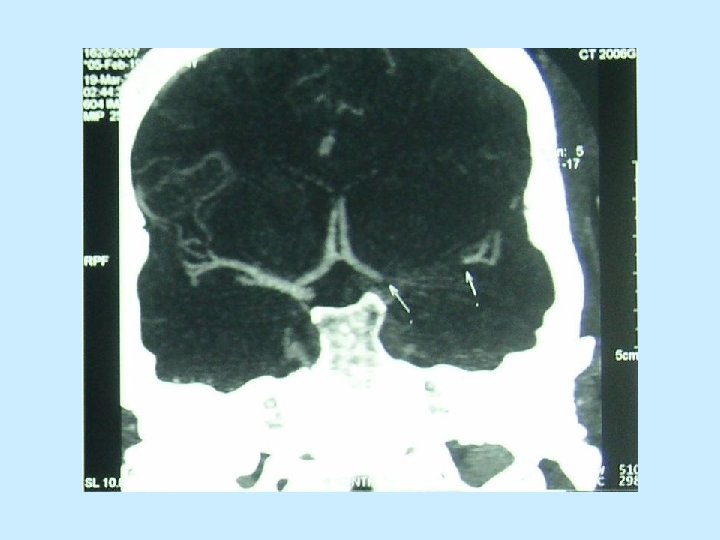

Indikátory mortality u pacientů s dekompresní hemicraniectomií • 5. Velikost ischemického ložiska v cm 3 zjištěné planimetrickou metodou v den operace. • 6. Velkost přetlaku střední čáry na CT snímku v den operace. • 7. Výsledný klinický stav zjištěný pomocí m. Rankinovi škály v době propuštění z nemocnice.